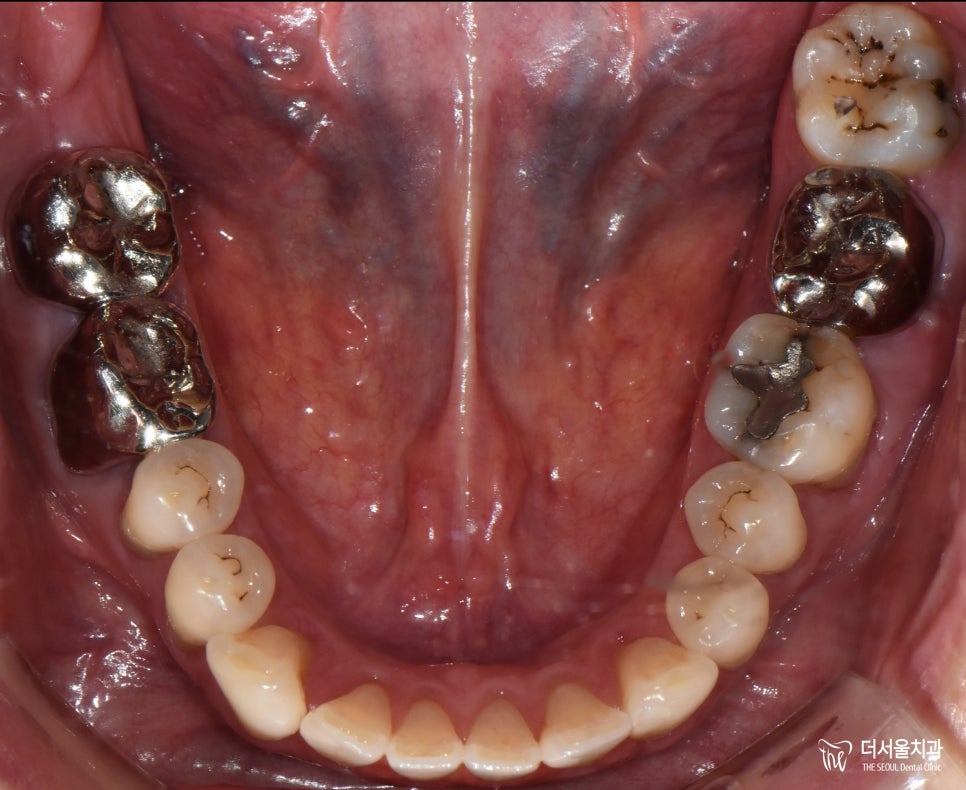

『초진』

첫 내원때 찍은 X-Ray인데,

여러분들께서는 어떤 곳이 문제가 있는지

찾을 수 있으실까요?

조금만 자세히 살펴봤을때,

그 답을 찾을 수 있습니다.

혹시 찾으셨을까요?

그럼 답을 한 번 확인을 해보겠습니다.

전체 구강을 보면 이런 상태인데,

그냥 보면 확인이 어렵죠?

명확히 나타나면 좋을텐데,

그렇지 않은 케이스도 있어서

파노라마와 함께 체크해볼 수밖에 없습니다.